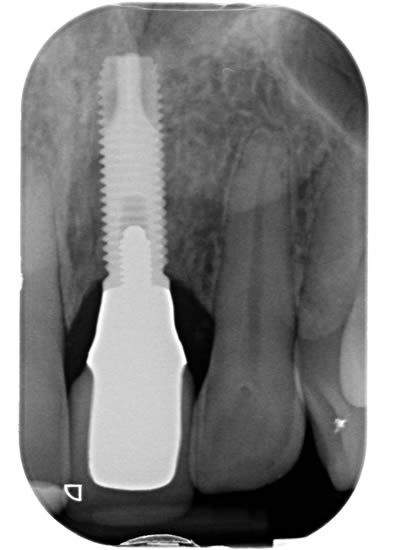

Missing upper front tooth replaced by dental implant and crown